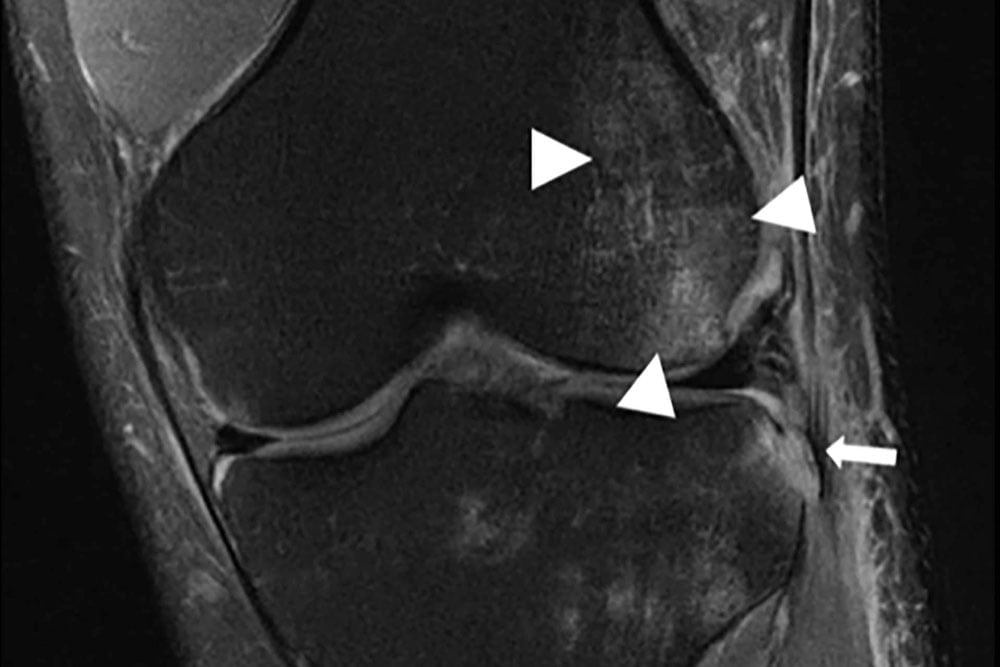

Jetzt stellen die Forscher die Ergebnisse ihrer Arbeit vor: Die mit reduzierten Daten aufgezeichneten und durch die KI ergänzten MRT-Bilder konnten in einem Blindversuch Radiologen überzeugen.

Für den Test bekamen klinische Radiologen über einen Zeitraum von zwei Jahren sowohl traditionell aufgenommene MRT-Bilder als auch KI-gestützte Aufnahmen zu sehen, ohne die Quelle zu kennen.

Die Studie fand keine signifikanten Unterschiede bei den Diagnosen der Radiologen, die dazu einstimmig die Bildqualität der KI-Aufnahmen als besser bewerteten.

Fünf von sechs Radiologen konnten nicht erkennen, mit welcher Methode die jeweiligen Bilder erzeugt wurden. Alle Aufnahmen stammen von sogenannten 3-Tesla-Geräten.

Die im Vergleich zur traditionellen Methode besser bewertete Qualität der KI-generierten Bilder erklärt der beteiligte Forscher Larry Zitnick: "Da die KI von MRT-Bildern lernt, wie typische Knie aussehen, kann sie das Aussehen des MRT verbessern, indem sie Rauschen oder andere Artefakte entfernt und die gelernten Strukturen stärker betont.“